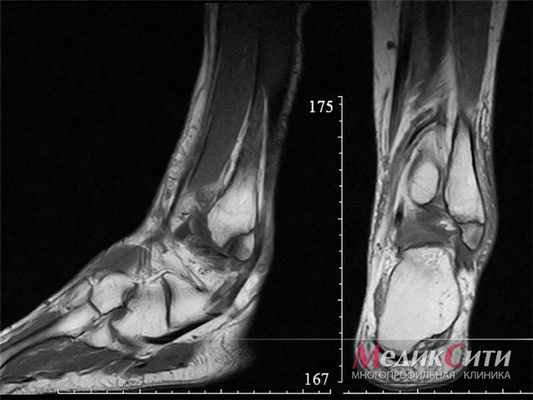

МРТ голеностопа: перелом лодыжки